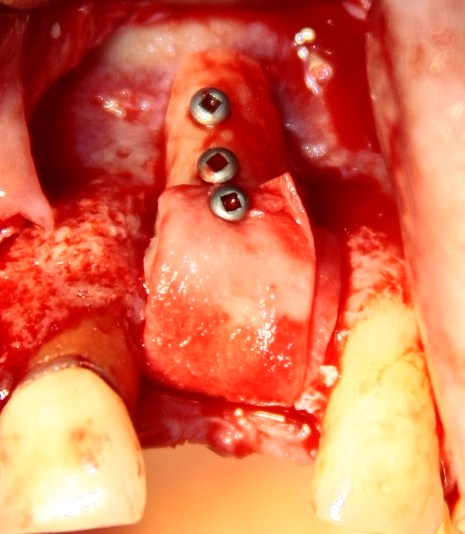

Если вы когда-нибудь видели подобные операции, то наверняка обращали внимание на порядок действий — сначала устанавливаются имплантаты, затем укладывается графт и только потом фиксируется мягкотканный аутотрансплантат. Для удобства в этом и похожих клинических ситуациях мы поменяли порядок действий:

Сначала мы провели и зафиксировали деэпителизированный соединительнотканный аутотрансплантат (ССТ). Для этого мы сформировали тоннель и использовали ортодонтическую проволоку в качестве проводника. Подробнее об этой методике можно почитать здесь>>.

Затем уложили ксенографт. Особенностями Bio-Oss Collagen являются удобство адаптации, устойчивость к вымыванию и выдавливанию, поэтому мы просто уложили полученные ранее пирамидки вестибулярно относительно будущего имплантата, после чего прижали их с помощью уже упоминавшихся аналогов имплантата, входящих в хирургический набор имплантационной системы Xive (кстати, при работе с другими имплантационными системами для паковки графта в лунке можно использовать круглые остеотомы для синуслифтинга).

В совокупности, аугментация лунок перед установкой имплантатов занимает около 20 минут — и это самый долгий из всех хирургических этапов лечения.